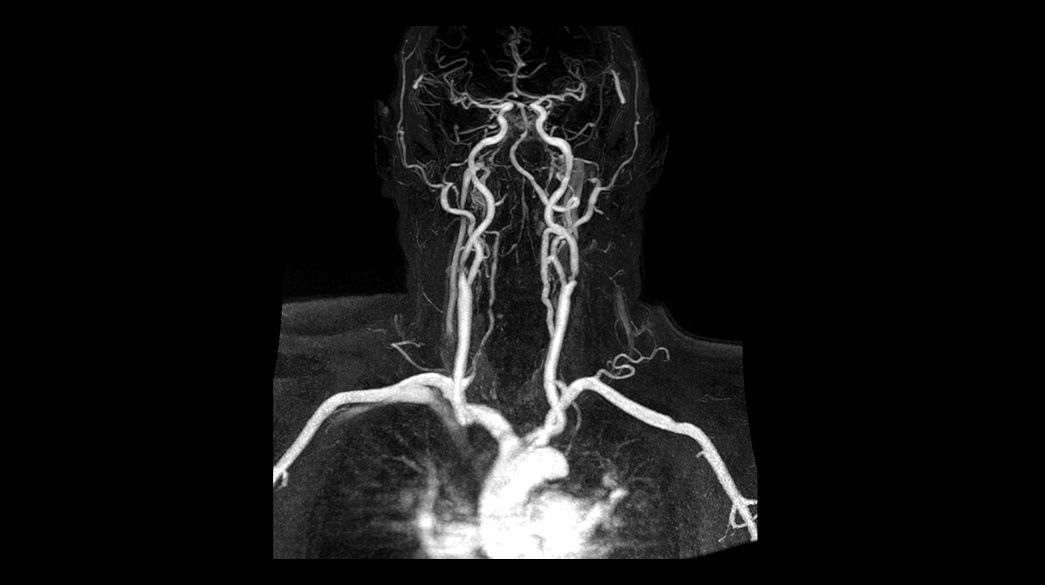

Fluoro Trigger MRA

Fluoroscopic triggering is a real-time bolus detection method of contrast arrival for vascular scans.

TRICKS

MR Angiography imaging that helps accelerate the temporal domain of 3D dynamic imaging – without compromising spatial resolution.

Inhance Suite

Improves workflow with easy setup through visualization of blood flow in diverse anatomies. Includes: 3D IFIR, 3D Velocity, 2D InFlow, 3D DeltaFlow